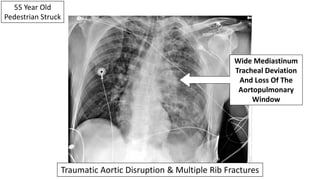

55 Year Old

Pedestrian Struck

Wide Mediastinum

Tracheal Deviation

And Loss Of The

Aortopulmonary

Window

Traumatic Aortic Disruption & Multiple Rib Fractures